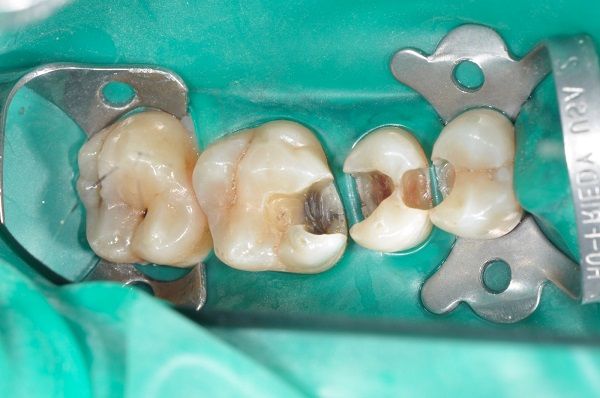

Definizione in breve

E’ un processo patologico irreversibile ad eziologia multifattoriale, che provoca la distruzione dei tessuti duri del dente (smalto, dentina e cemento) con complicanze di ordine locale (pulpiti, parodontiti) e

sistemico (malnutrizione e disturbi dell’apparato gastrointestinale).